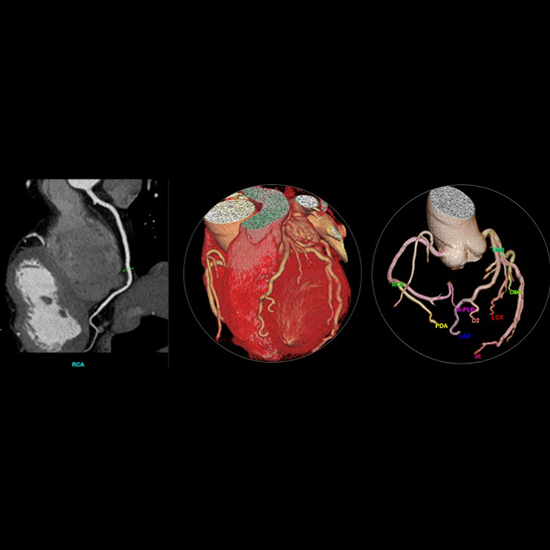

Anatom 64 Clarity, kardiyak görüntülemede giriş seviyesindeki rakiplerine oranla daha düşük doz ile daha yüksek kaliteli görüntüler sunan teknolojik donanımlara sahip 64 kesit bir bilgisayarlı tomografi sistemidir.

Yüksek zamansal çözünürlük sunarak kullanıcı deneyimini iyileştiren Anatom 64 Clarity, aynı zamanda 5.3 MHU'luk tüpü sayesinde 120 saniyeye kadar devamlı çekim imkanı sunar ve tüm gün çekimlerde herhangi bir sorun yaşanmamasına olanak tanır.

Görüntü bozulmalarını engelleyecek yazılımlara sahip olan Anatom 64 Clarity, farklı klinik ihtiyaçlara uyum sağlayabilmesi için dijital ve mekanik eğim ayarlarına sahiptir ve gerçek zamanlı çarpışma önleme sistemleriyle hasta güvenliğini de sağlar.